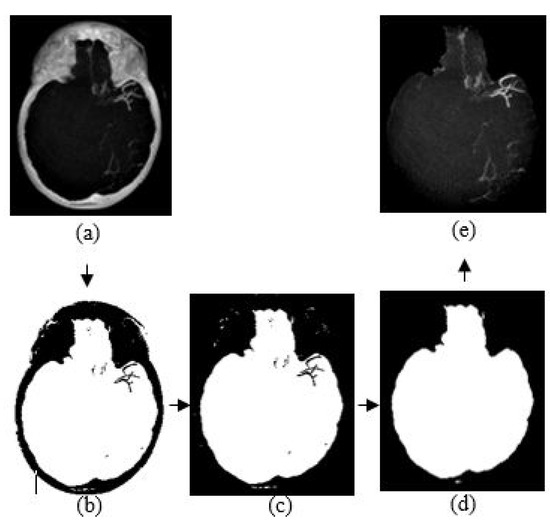

3.4. Skull Removal

3.5. Noise and Artifact Removal

4.2. Artifact Removal